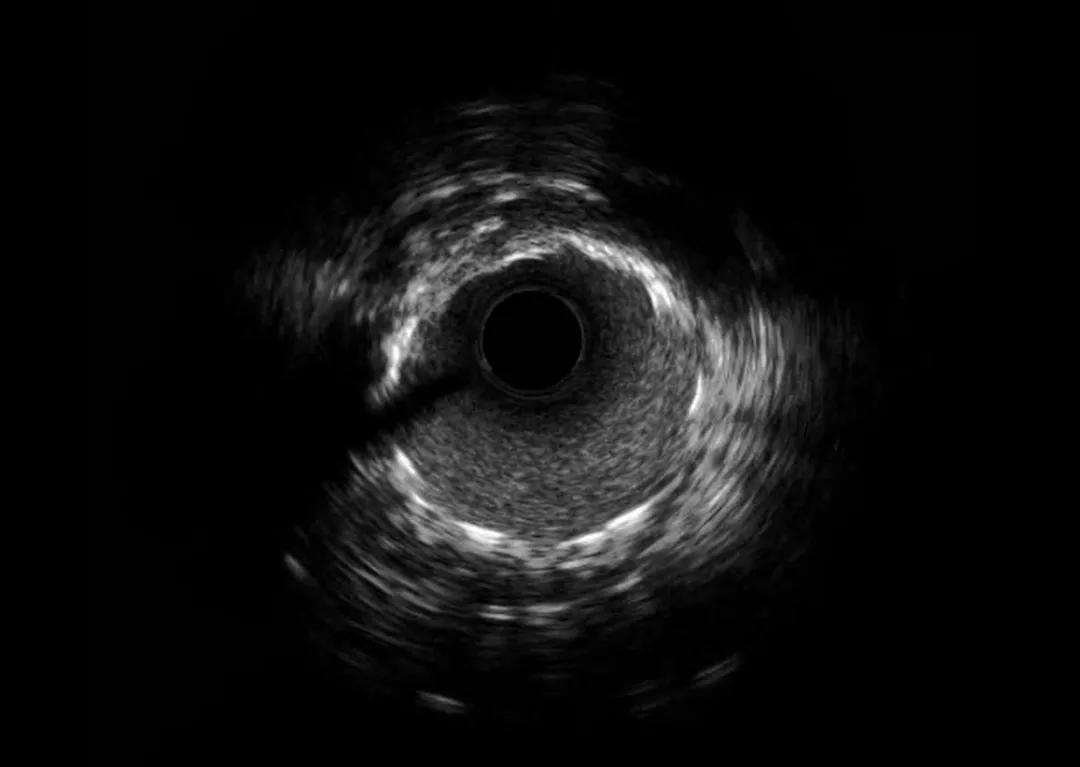

与患者交代病情,反复沟通,患者终因对这种非常规操作的忐忑犹豫,选择了药物治疗。 然而,两周后,因更加频繁发作的胸痛,焦虑和痛苦,该患者再次来到我院心血管内科门诊,要求手术治疗。 经过充分的术前准备,周密制定的手术方案,以及手术推演,8月26日下午,韩江莉顺利经桡动脉入路为患者进行了IVUS检查。结果显示,左前降支最小管腔面积仅1.86mm2,伴有270°钙化。经使用切割球囊充分预扩张后顺利植入支架。IVUS检查提示,支架膨胀及贴壁良好,无边缘夹层等情况。

术后血管内超声(IVUS)显示支架膨胀完全,支架边缘没有夹层,手术成功。